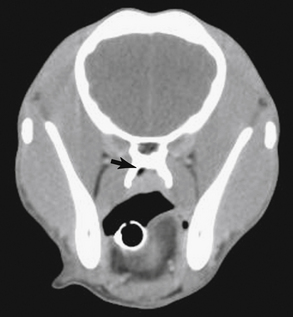

Radiography

Radiographic imaging or CT is always performed before rhinoscopy. Rhinoscopic iatrogenic hemorrhaging and irrigation fluid used during the procedure will distort tissue and create fluid densities that can influence the findings in any radiographic study. Nasal radiographs can be performed in most hospitals and, with practice, can be very useful in the localization and characterization of nasal and nasopharyngeal disease.5 Nasal radiographs require general anesthesia and special patient positioning. Most commonly performed are 30-degree beam-angled open-mouth ventrodorsal and straight lateral views. The open-mouth view provides a complete, symmetrical image of the nasal cavity without superimposition of the mandible. Tumors typically show asymmetrical opacities and turbinate destruction (Figure 19-6). Turbinate destruction is also seen with fungal rhinitis. The straight lateral view allows evaluation of the nasopharynx and frontal sinuses (Figure 19-7). Further study of the frontal sinuses is achieved with a rostrocaudal tangential view (Figure 19-8). This allows comparison of the left and right frontal sinuses as the cavities are superimposed on the lateral view. Dental films of the maxillary arcade are sometimes needed to rule out tooth root abscesses and oronasal fistulae. MRI and CT scans are becoming more commonly available and provide better detail of the nasal, nasopharyngeal, and sinus cavities and cranial vault anatomy compared with standard radiography.6,7 Advanced imaging via MRI and CT, although considered state of the art, assist in description and localization of diseased tissue but have not yet produced results specific enough to eliminate the need for rhinoscopy8,9 (Figures 19-9 through 19-11) (Table 19-1).

Figure 19-9 Feline skull computed tomography image with nasopharyngeal mass.

image